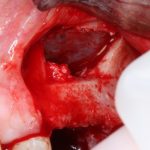

Если на этапе разреза и формирования раны всё сделано правильно, то наложение швов не вызывает особых трудностей. Периостотомия или послабляющие разрезы на периосте не требуются (ни практически никогда не требуются). А сами швы получаются аккуратными и герметичными:

Обрати внимание, что все шовные лигатуры находятся в пределах кератинизированной десны. Это позволяет избежать деформации тканей и лишних рубцов. В наиболее уязвимых местах (около зубов) шовные лигатуры лучше продублировать.

Если бы мне пришлось делать это сейчас, то я бы использовал непрерывный «матрацный» шов. Он удобнее, быстрее в наложении и комфортнее для пациента. Минус — если распускается, то распускается весь. К тому же, его очень неудобно снимать.

Несмотря на то, что уже тогда мы широко использовали непрерывные швы в подобных случаях, здесь я, во-первых, зассал (может распуститься), во-вторых, снятие швов предполагалось в поликлинике по месту жительства пациентки, и мне не хотелось, чтобы там при снятии швов начудили. Как выяснится позже — зря беспокоился.

Неизменно одно — в таких операциях мы использовали и до сих пор используем нерезорбируемые монофиламентные шовные материалы, поскольку они наиболее гигиеничные. Чтобы острые концы нитей не беспокоили пациента, их можно оплавить нагретой гладилкой или гуттаперчевым плаггером.